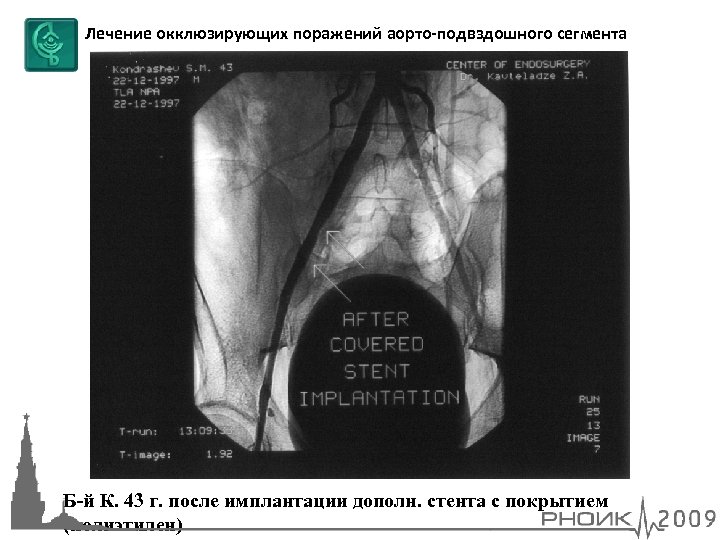

Лечение окклюзирующих поражений аорто-подвздошного сегмента Б-й К. 43 г. окклюзия правой НПА, перфорация НПА после реканализации + БА + стентирования

Лечение окклюзирующих поражений аорто-подвздошного сегмента Б-й К. 43 г. после имплантации дополн. стента с покрытием (полиэтилен)